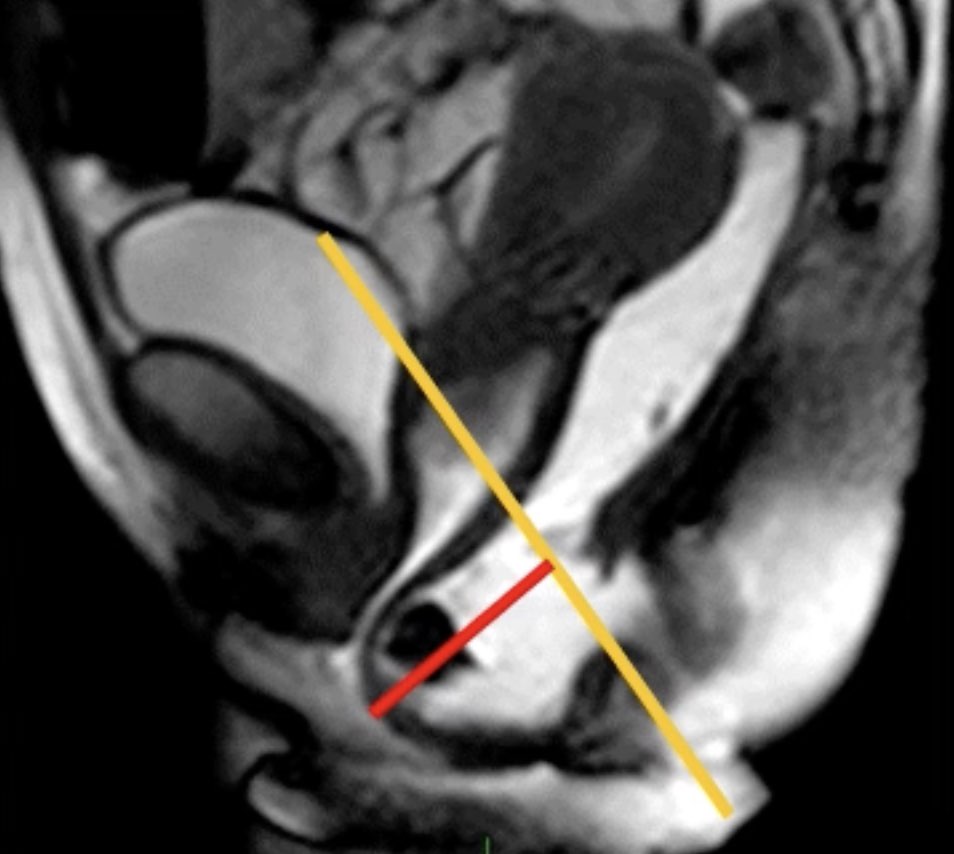

Rectocèle antérieure = rétentionniste ?

significative si > 2 cm de profondeur

significative si > 2 cm de profondeur

Prolapsus rectal (intussusception) = obstructif ?

2 = affleure le canal anal, 3 = intra-anal, 4 = extériorisé

2 = affleure le canal anal, 3 = intra-anal, 4 = extériorisé

→ même gradation pour les péritonéocèles rectales

Asynchronisme ano-rectal = anisme

fermeture paradoxale du muscle élévateur en poussée

fermeture paradoxale du muscle élévateur en poussée

Périnée descendant

> 6 cm sous la ligne pubo-coccygienne

> 6 cm sous la ligne pubo-coccygienne